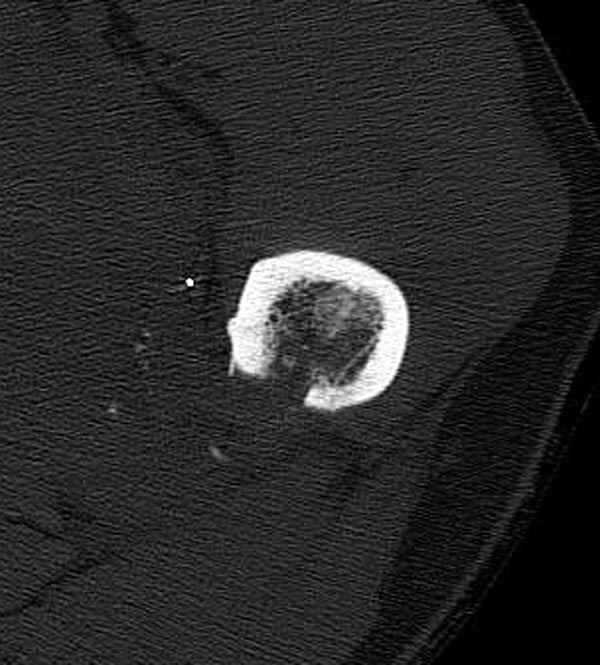

Больной с огнестрельным переломом бедра с вовлечением около 15% медиального кортекса, входное отверстие около 1 см в диаметре; стабильный, без сосудистых и неврологических признаков.

Методика штифтования при отсутствии большой зоны перелома как при онкологических профилактических штифтованиях, расверливание интрамедуллярного канала проводим с предварительным наложением дополнительного дренажного отверстия в дистальном отделе бедра (в данном случаи в канале оставили 6.5 мм канюлированный шуруп), иначе при создании давления в канале во время сверления имеется опасность эмболизации легочной артерии тромбом.